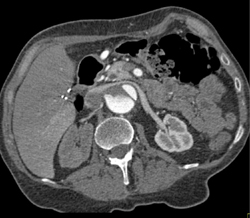

Pelvic Tumor Infiltration Encases the Bladder